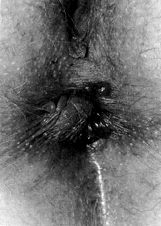

4.3.5 Gastroscopia

dell¹ulcera

Le ulcere vengono diagnosticate dal medico

specializzato tramite gastroscopia: